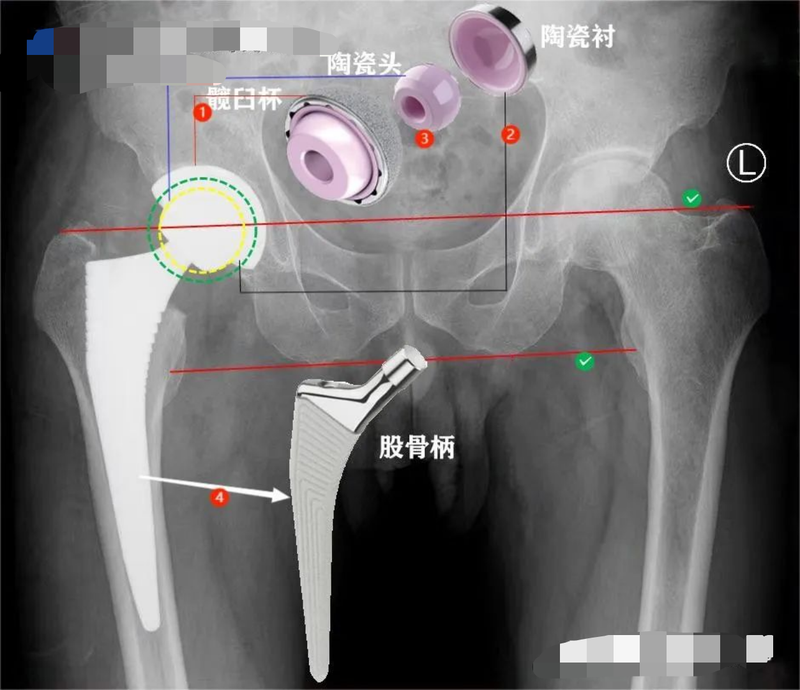

可能很多人對(duì)這個(gè)問題不屑一顧:肯定是進(jìn)口的好嘛!這個(gè)說(shuō)法猛一聽沒毛病。確實(shí),近代以來(lái)我國(guó)經(jīng)濟(jì)、科技、軍事......發(fā)展遠(yuǎn)遠(yuǎn)落后歐美太多,已經(jīng)給很多人造成了習(xí)慣性思維。不過嘛,環(huán)望寰球,中國(guó)已經(jīng)不是1840年的中國(guó),我們用幾十年的時(shí)間完成了其他國(guó)家200~300年才能完成的現(xiàn)代化進(jìn)程,他們已經(jīng)沒有實(shí)力跟我們這樣講話了。一聊國(guó)與國(guó)的比拼就容易讓人激動(dòng),接著聊聊今天的正事兒。髖關(guān)節(jié)置換以后一般是這樣的:人工髖關(guān)節(jié),分成兩大部分:固定組件和摩擦界面固定組件:髖臼杯①、股骨柄④,有時(shí)還會(huì)在臼杯上安裝釘子以輔助固定;磨損界面:髖臼內(nèi)襯②、股骨頭③,根據(jù)不同的配置,內(nèi)襯可以是陶瓷材質(zhì),也可以是聚乙烯或高交聯(lián)聚乙烯,股骨頭可以是金屬頭或陶瓷頭。所以,評(píng)價(jià)假體質(zhì)量可以從這兩方面入手01陶瓷界面很多人特別在乎關(guān)節(jié)是不是陶瓷股骨頭,事實(shí)上,這個(gè)問題最不是問題。市場(chǎng)上絕大多數(shù)陶瓷關(guān)節(jié)是德國(guó)CeramTec公司2003年推出的BIOLOX?delta氧化鋁基復(fù)合陶瓷(粉陶),BIOLOX?forte黃陶基本已退出市場(chǎng)。Smith&Nephew公司的黑晶陶瓷頭則占據(jù)一定的市場(chǎng)份額。日本京瓷的藍(lán)陶則更是鮮有耳聞相應(yīng)的,髖臼內(nèi)襯一般為聚乙烯或高交聯(lián)聚乙烯,或者陶瓷內(nèi)襯。美國(guó)“軟陶”關(guān)節(jié)需要注意的是,并不是全陶瓷摩擦界面的關(guān)節(jié)最好,比如對(duì)于農(nóng)村老年女性,生活中需要下蹲如廁、從事農(nóng)活,半陶瓷關(guān)節(jié)不僅耐磨損,而且更降低了脫位的風(fēng)險(xiǎn)。再者,選擇關(guān)節(jié)還要看具體病人,某些發(fā)育異常、身材矮小的病人并沒有充足型號(hào)的關(guān)節(jié)可供選擇。目前,全世界絕大多數(shù)人工關(guān)節(jié)廠家選用的陶瓷均來(lái)自德國(guó)CeramTec公司,所以,無(wú)論美國(guó)關(guān)節(jié)還是中國(guó)關(guān)節(jié),第四代粉陶都是一樣一樣的。02固定組件如同蓋房子,再好的室內(nèi)設(shè)計(jì)、再漂亮的玻璃幕墻,如果沒有扎實(shí)穩(wěn)固的地基作支撐,一切都會(huì)成為海市蜃樓。行外人往往只關(guān)注股骨頭和內(nèi)襯能磨損多少年,卻忽略了磨損其實(shí)是建立在髖臼、股骨柄能否與骨床牢固結(jié)合、融為一體的基礎(chǔ)上——假體表面處理技術(shù)至關(guān)重要。某進(jìn)口品牌髖臼假體的做工:某國(guó)產(chǎn)品牌髖臼假體的做工:該品牌除了與進(jìn)口產(chǎn)品同樣水平的表面處理技術(shù)外,還精心設(shè)計(jì)了釘孔封堵帽,這些細(xì)節(jié)很暖心。某進(jìn)口品牌股骨假體的做工:某國(guó)產(chǎn)品牌股骨假體的做工:能看出進(jìn)口與國(guó)產(chǎn)的區(qū)別嗎?國(guó)產(chǎn)的是不是更秀氣些?想想看,國(guó)人與歐美人體型是不是有差別?需要強(qiáng)調(diào)一點(diǎn),國(guó)產(chǎn)假體制造工藝上不是在模仿,而是一直按照國(guó)際標(biāo)準(zhǔn)進(jìn)行......03面子很重要,里子更要看假體材質(zhì)、表面處理技術(shù)是評(píng)價(jià)質(zhì)量的重要方面,關(guān)節(jié)的設(shè)計(jì)是否能滿足病人需求則是醫(yī)生更加關(guān)注的問題。大千世界,每個(gè)人除了長(zhǎng)相不同之外,身高更是參差不齊,相應(yīng)的髖關(guān)節(jié)各解剖參數(shù)也不盡相同。這就決定了一個(gè)品牌的關(guān)節(jié)假體不可能適用于所有病人。關(guān)節(jié)設(shè)計(jì)的主要參數(shù)醫(yī)生的重要性就體現(xiàn)出來(lái)了:為病人選擇最合適的關(guān)節(jié)。否則,就會(huì)出現(xiàn)片子很美、病人很不爽的尷尬結(jié)果。如下面的案例1:病人之前選用國(guó)產(chǎn)某小眾品牌關(guān)節(jié)做了左側(cè)置換,術(shù)后下肢變長(zhǎng),又因長(zhǎng)時(shí)間臥床導(dǎo)致廢用性骨質(zhì)疏松,髖臼安裝過高致旋轉(zhuǎn)中心上移出現(xiàn)行走乏力、不協(xié)調(diào),假體近端過寬、應(yīng)力大導(dǎo)致大腿痛;我們采用了另一品牌的關(guān)節(jié),根據(jù)對(duì)側(cè)情況適當(dāng)調(diào)整了肢體長(zhǎng)度、旋轉(zhuǎn)中心,使得雙下肢能夠在行走時(shí)協(xié)調(diào)一致,且選擇了合適的假體,避免了股骨近端應(yīng)力集中,術(shù)后第2天下地行走,避免了廢用性骨質(zhì)疏松;病人明顯體驗(yàn)不一樣的手術(shù)效果。再如案例2:病人施行的是進(jìn)口全陶瓷髖關(guān)節(jié)置換術(shù),術(shù)后訴術(shù)側(cè)延長(zhǎng)2cm,行走特別不舒服,進(jìn)行康復(fù)治療較長(zhǎng)時(shí)間亦無(wú)明顯改善;盡管從影像看雙下肢等長(zhǎng)——卻改變了髖關(guān)節(jié)解剖(旋轉(zhuǎn)中心上移、略內(nèi)翻)。所以,很多情況不是錢的問題,不是進(jìn)口的越貴越好,合適的才是最好。正如農(nóng)村人買車,既要往城里跑,也要下莊稼地,那么,皮卡就是最好的選擇。04結(jié)論進(jìn)口關(guān)節(jié)依據(jù)歐美人種解剖數(shù)據(jù),假體材質(zhì)質(zhì)量整體較高;國(guó)產(chǎn)高端關(guān)節(jié)和進(jìn)口關(guān)節(jié)陶瓷部件質(zhì)量零差別,但產(chǎn)品設(shè)計(jì)來(lái)自國(guó)人解剖數(shù)據(jù),更適合多數(shù)人;國(guó)產(chǎn)低端關(guān)節(jié)一直在模仿,總有一天會(huì)超越;在質(zhì)量無(wú)顯著差異的情況下,選擇一款不太匹配的進(jìn)口關(guān)節(jié)顯然不是特別理智的事兒。